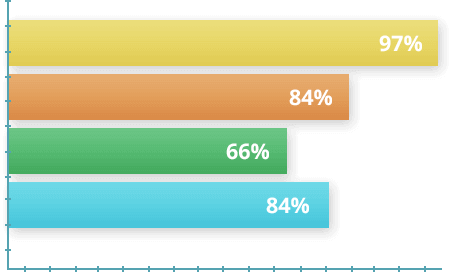

În 2017, au fost efectuate studii cu participarea a 1.700 de voluntari cu diferite grade a bolii articulare. Conform condițiilor, subiecții au utilizat REMOFIX timp de 30 de zile. La sfârșitul experimentului, statisticile au fost compilate pe baza datelor obținute.

- 97% dintre participanți a simțit o ușurare rapidă a durerii

- 84% dintre participanți au scăpat de probleme articulare în 1 curs

- 66% dintre participanți după finalizarea cursului s-au întors la sport

- 84% dintre participanți au remarcat îmbunătățirea mobilității articulare, comparativ cu starea înainte de curs